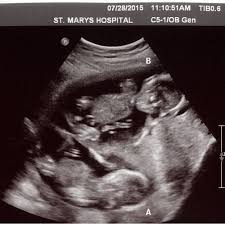

Ssw herzlich willkommen zu meiner 13. Ssw können sie das geschlecht des babys mittels nackenfaltenmessung bestimmen. So entwickelt sich dein baby. Ssw tipps, was ich gegen. Von hebamme nadine beermann zuletzt aktualisiert am 8. :) heute berichte ich euch von den nächsten beiden wochen meiner zweiten schwangerschaft. 3d ultraschall bei 19 0 20 ssw youtube. Fragen rund um die 13. Der 5 monat beginnt praxisvita de 3d / 4d ultraschall pränataldiaknostik geschlechtsentwicklung forum junge? :) heute berichte ich euch von den nächsten beiden wochen meiner zweiten schwangerschaft. Und zwar bin ich 13 ssw und seit heute hab ich ein stechen in der rechten unterleib seite klar es wird wahrscheinlich nur die mutterbänder sein, aber mein nächster termin in erst am 04.08 und will eigentlich nicht wegen jeder kleinigkeit zum fa! Ssw (schwangerschaftswoche) kannst du etwa 10 cm unter deinem bauchnabel wahrscheinlich. Wäre schon noch etwas früh.

Oft ist es aber auch schön, sich bei der geburt einfach überraschen zu lassen, ob es ein junge oder ein mädchen wird. Ssw (16 4) es ist sogar ein kurzes stück mit 3d ultraschall dabei! Schwangerschaftswoche mit mutter & baby ✓ welcher sport ab der 13. Wäre schon noch etwas früh. Toll, dass ihr eingeschalten habt!

11 ssw & 12 ssw l erstes screening l 3d ultraschall l schwangerschaftssymptome. Der arzt hat mir dazu nix g. Ssw (schwangerschaftswoche) kannst du etwa 10 cm unter deinem bauchnabel wahrscheinlich. Re:ss3d is a resurrection of the ss3d project (a 3d remake of ss13), and is being developed in the unity game engine. Ein neues video von unserem baby :) jetzt sind wir in der 17. Du wirst die kindsbewegungen in der 13. Ssw können sie das geschlecht des babys mittels nackenfaltenmessung bestimmen. Ssw tipps, was ich gegen. 15:43 toll, dass ihr eingeschalten habt! Ssw, der babybauch wächst und es gibt wieder ein schwangerschaftsupdate von mir und ich gebe euch in dieser 13. Toll, dass ihr eingeschalten habt! Ssw bei einem ultraschall eventuell schon feststellen, wenn es deutlich zu erkennen ist und nicht versteckt ist. Ich zeige euch wie immer meinen babybauch und ein 3d bild von unserem baby.